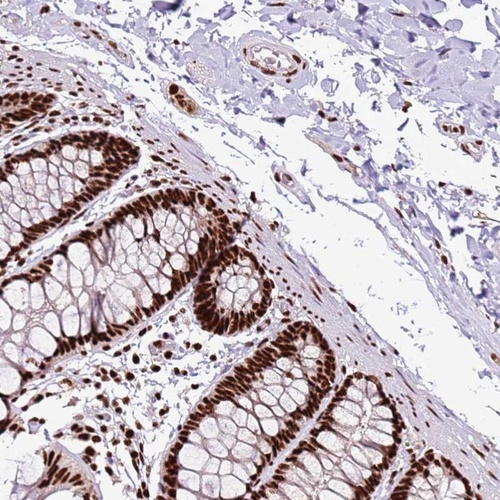

Immunohistochemical staining of human colon shows strong nuclear positivity in glandular cells and ganglion.